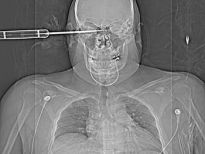

Şoke eden röntgen filmleri

Bu röntgen filmleri görenleri şaşkına çeviriyor!